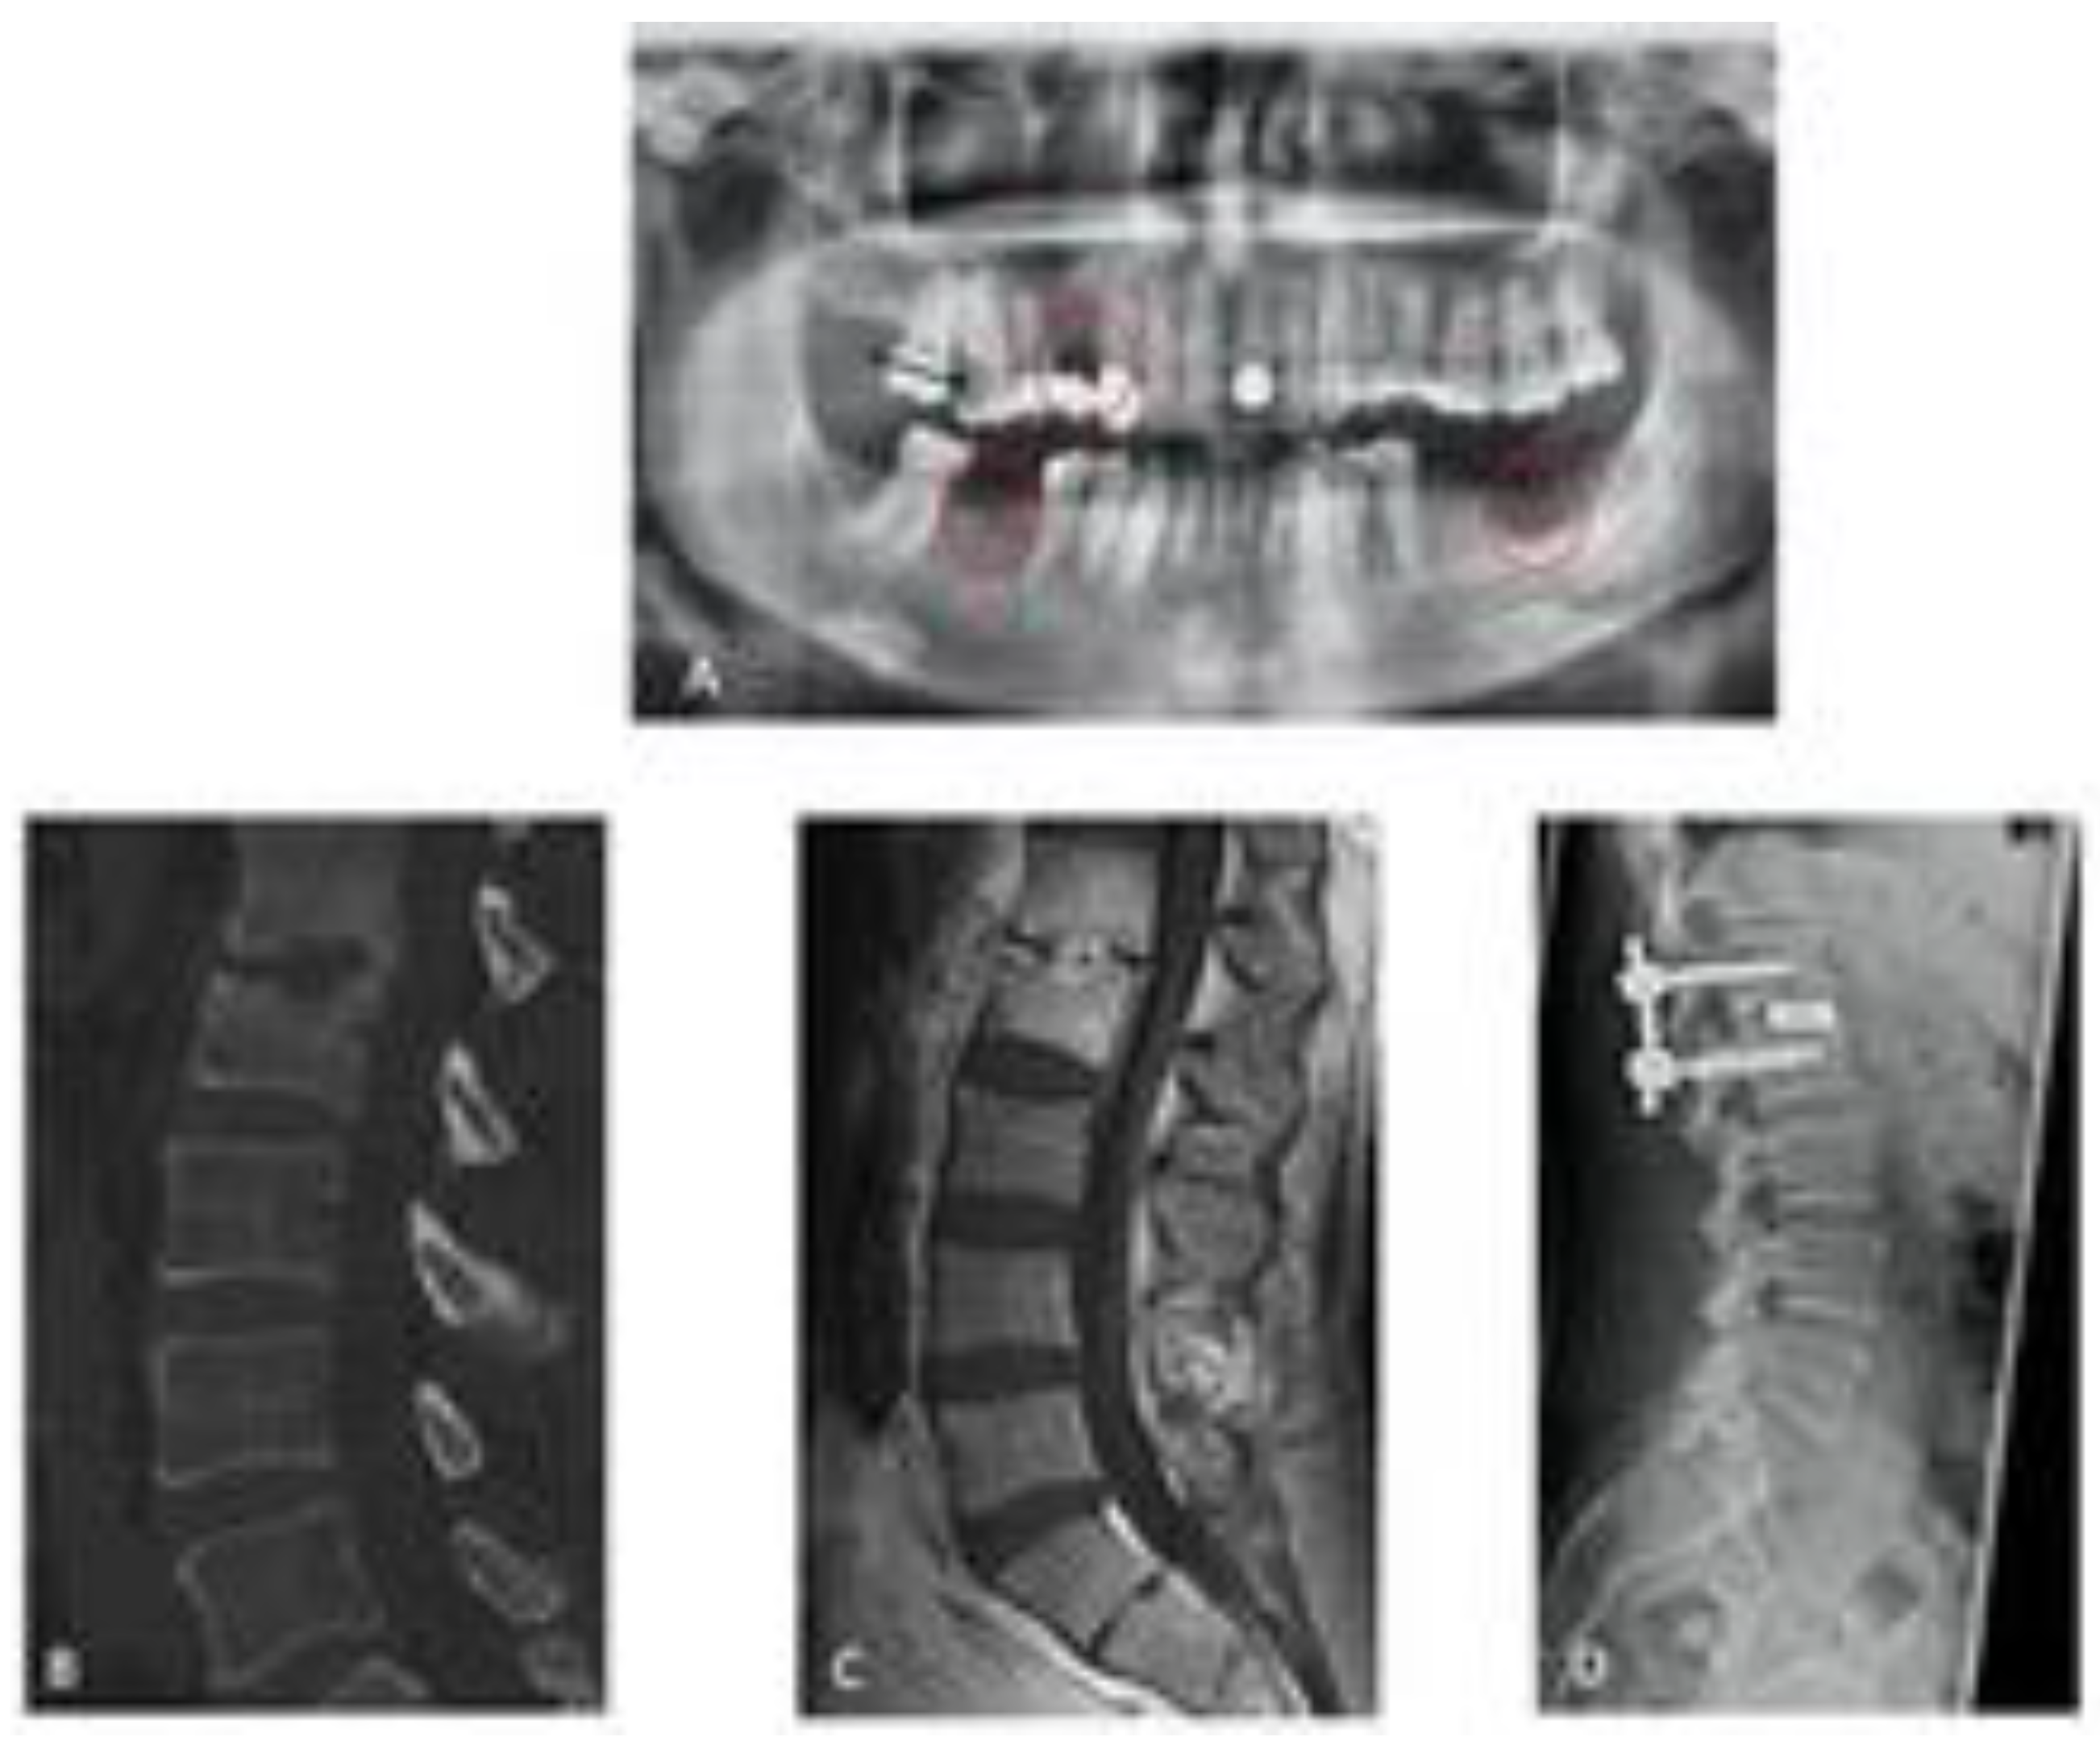

In addition to treating the spinal infection, optimal care also includes identifying the source of the pyogenic spinal infection as well as the presence of other infections. In a prospectively conducted study with systematic radiological and dental examinations, we were able to demonstrate that more than 50% of the patients with spondylodiscitis undergoing OPG had an infection of the oral cavity (Figure 4).

Figure 4.

Spondylodisciits and oral cavitiy infection ((A) OPG with an infection of the oral cavity/red circels), (B,C) CT/MRT with bony destruction, (D) CT after surgical treatment of discitis).